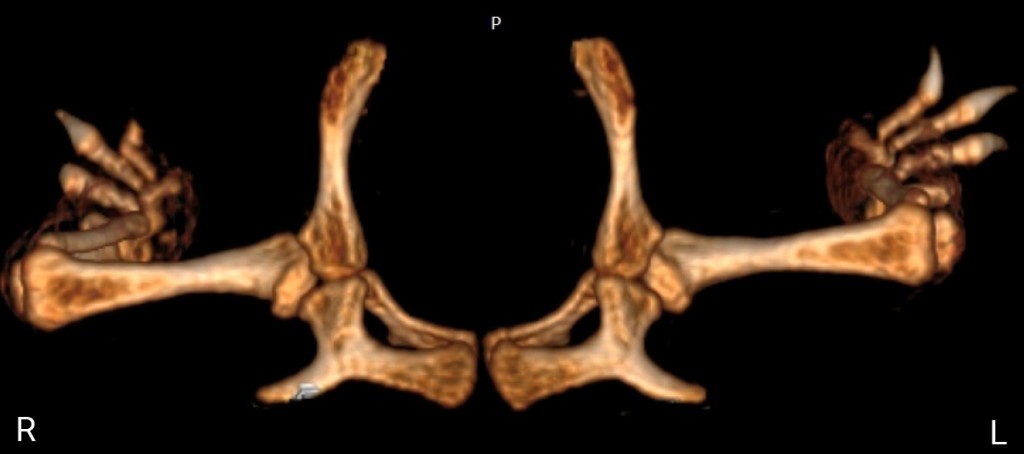

Спустя 12 часов после хирургического вмешательства животному была повторно выполнена процедура компьютерной томографии. Послеоперационная КТ показала нормальное анатомическое расположение головки бедренной кости относительно вертлужной впадины (фото 10, 11). Ограничение подвижности прооперированной конечности не проводилось. Спустя 24 часа черепаха была выписана домой.